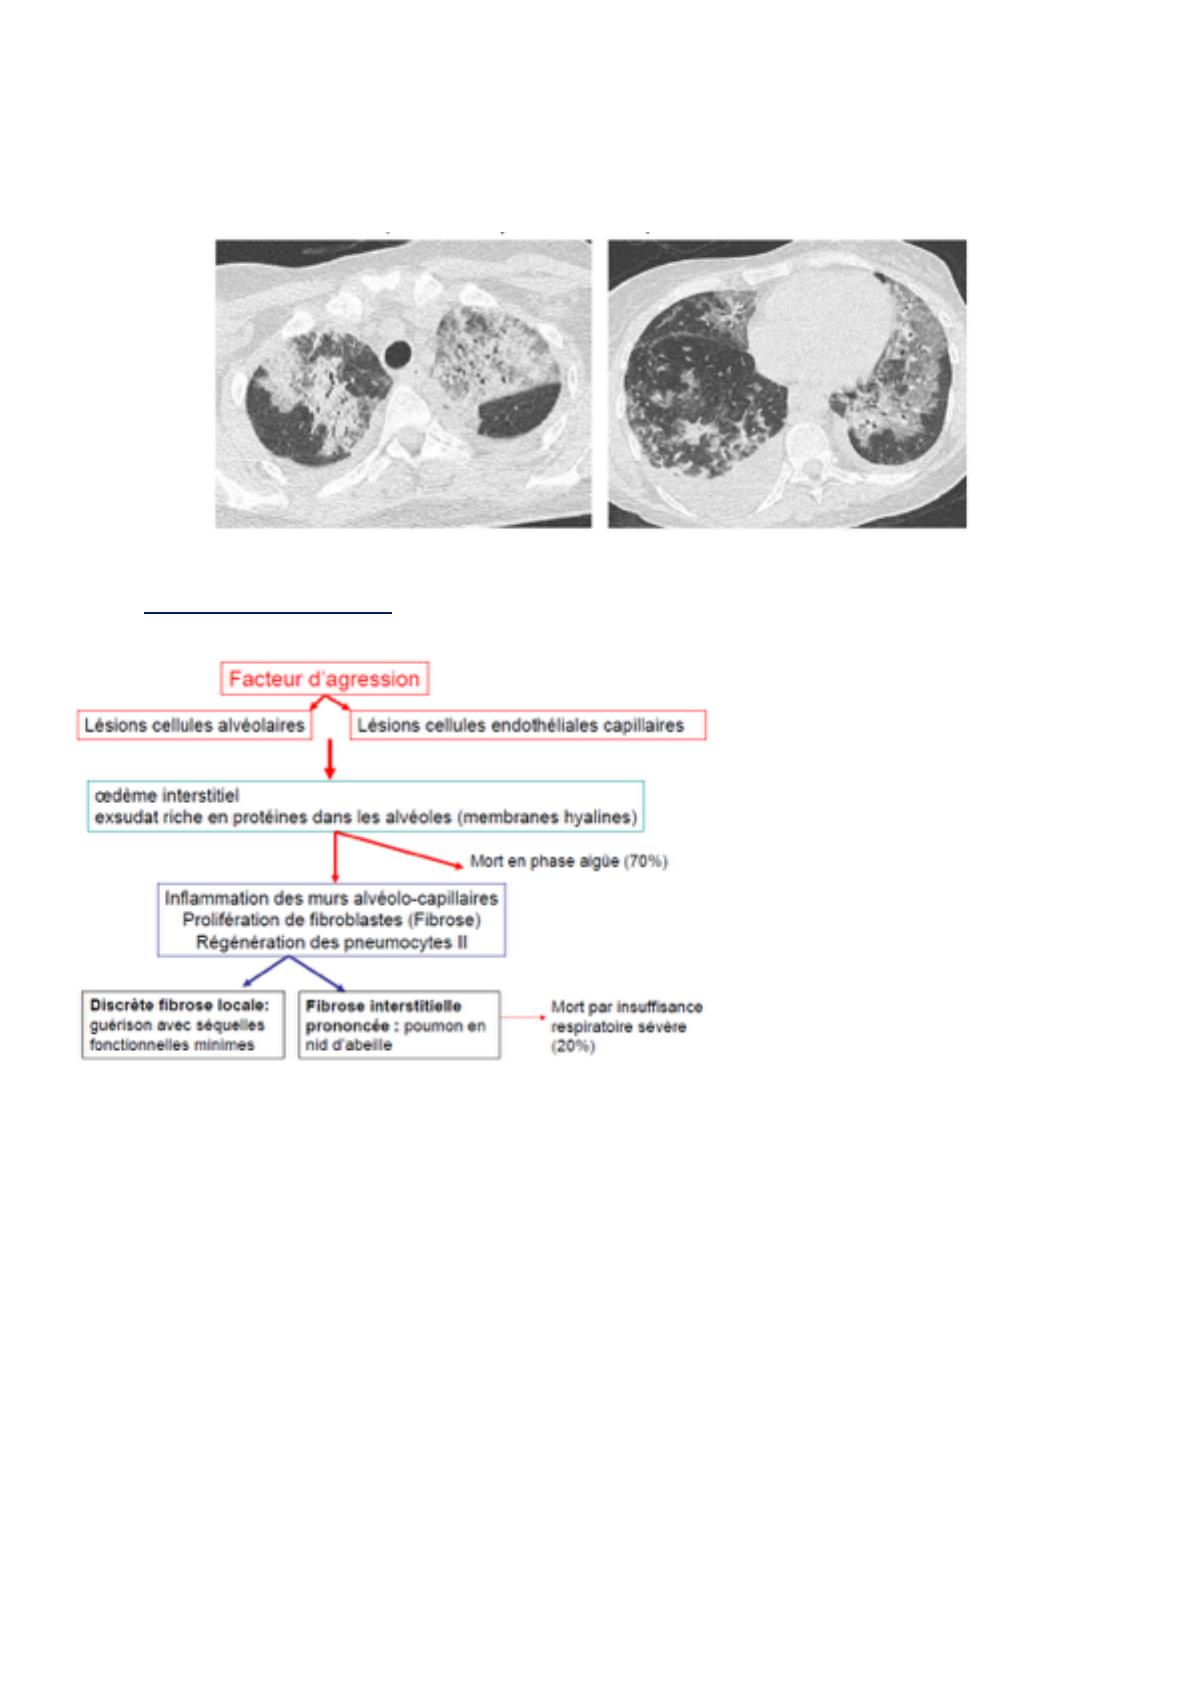

Dans la DRA, quel que soit le facteur d'agression (toxique, infectieux ou autre), il va y avoir une agression à

la fois des cellules alvéolaires (pneumocytes) et des cellules endothéliales des capillaires qui circulent dans

les murs alvéolaires. Cette double agression va être responsable d'un afflux de liquide dans les alvéoles qui

va passer des capillaires aux alvéoles, formant un œdème : les alvéoles sont remplies de liquide au lieu

d’être vides.

En parallèle, sur les parois des alvéoles il y aura formation d'un exsudat (fait de protéines amenées par

l'inflammation), formant la membrane hyaline. S'il y a la membrane hyaline qui tapisse le mur alvéolaire, la

barrière alvéolo-capillaire fonctionne très mal. A ce stade, il peut y avoir soit décès soit le poumon va être en

inflammation et cicatrisé. Il va y avoir une prolifération de fibroblastes (fibrose) pour réparer les dommages

alvéolaires. Dans un deuxième temps, il y aura régénération des pneumocytes.

La fibrose peut être momentanée et se résoudre favorablement, sans séquelle, soit la fibrose est très

importante et on va avoir un poumon en nid d'abeille car tous les murs alvéolaires sont remplacés par de la

fibrose. Dans ce cas de fibrose interstitielle prononcée, 20 % des patients risquent de mourir à terme par

insuffisance respiratoire sévère. Le mécanisme est quasiment le même quelle que soit l'étiologie, en sachant

qu'il y a des facteurs d'agression plus ou moins importants.